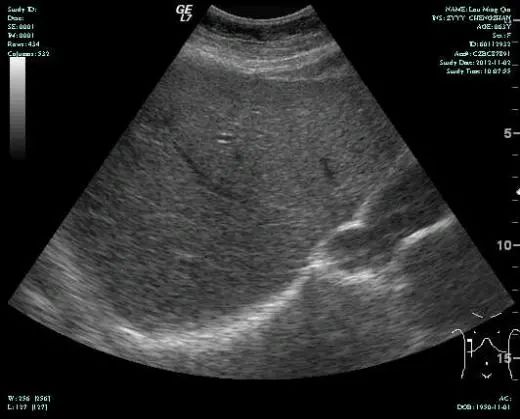

MR-H1

影像学检查结果评估:cPD。

• 第三次FOLFOX+T方案后 B超提示肝转移灶消失